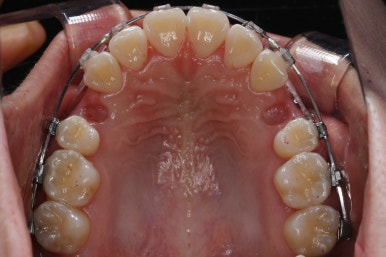

다시 이번 환자분으로 돌아가, 입 안모습을 보시겠습니다.

부산무턱교정 키다리아저씨치과에서 처음 내원하셨을 당시의 입 안의 모습입니다.

아래턱이 작아서 상대적으로 윗니들이 많이 돌출되었고, 뻐드러져 있습니다. 윗니들이 배열되어 있는 형태도 V자에 가깝게 입천장이 좁은 양상입니다.